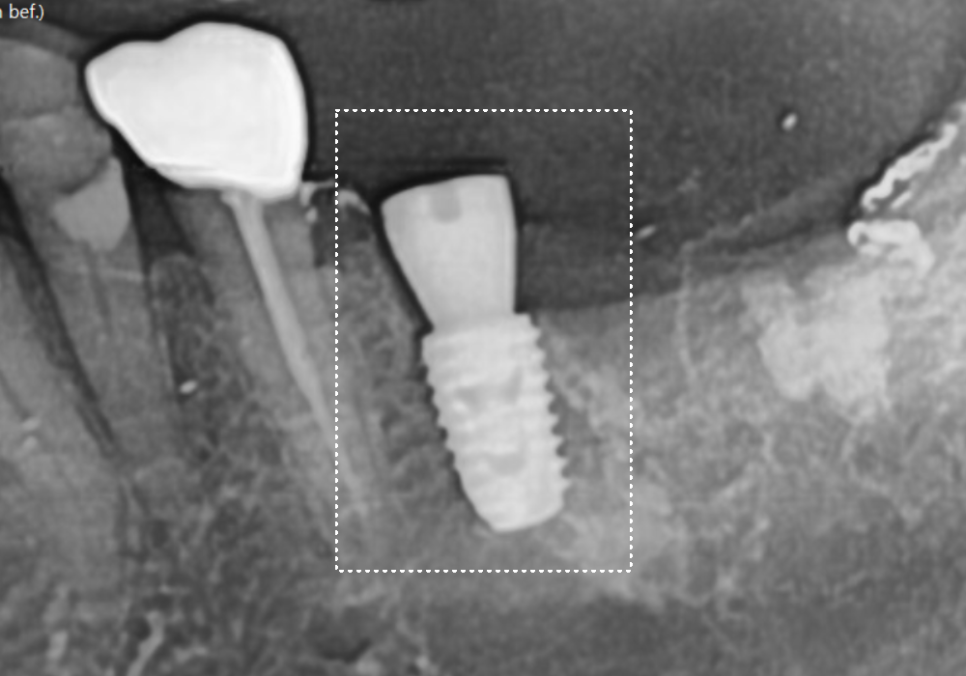

241015

덕분에 치료 기간을 대폭 단축할 수 있었는데요.

발치 당일 임플란트를 심고,

뼈와 잘 붙기를 2개월 정도 기다린 뒤

본을 떠서 보철물까지 올려드렸습니다.

241212

발치부터 최종 치아가 완성되기까지

딱 2개월이 소요된 셈이죠.